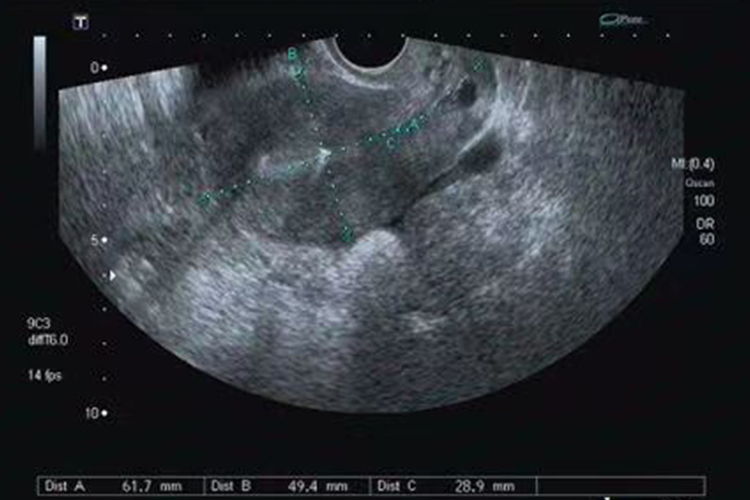

做腹部B超时,发现两次B超子宫位置不一样,这可能是体位和膀胱的压迫程度的不同导致的,属于正常现象。此外,盆腔炎性疾病也可能导致子宫向后倾倒,主要表现为腰部酸胀不适、小腹疼痛、肛门坠胀感,月经过多等。若得不到及时矫正,还可继发痛经、月经不调、不孕等。

盆腔炎性疾病,如发生子宫内膜炎、输卵管炎或输卵管卵巢囊肿时,感染导致纤维素脓性渗出物增多,导致子宫体和后方的直肠之间组织粘连,使子宫在牵引作用下脱离原来位置而向后倾倒,出现两次B超子宫位置不一样的情况。